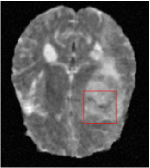

Qualitative comparison between conventional and Meta-learning methods are shown in Figure 1 and 3, which display the reconstructed MR images of the same slice for T1 and T2 respectively, we label the zoomed-in details of HGG in the red boxes. We observe the evidence that conventional learning is more blurry and lost sharp edges, especially in lower CS ratios. From the point-wise error map, we find meta-learning has the ability to reduce noises especially in some detailed and complicated regions comparing to conventional learning.

In this section, we test the generalizability of the proposed model that tests on unseen tasks. We fix the well-trained task-invariant parameter and only train for sampling ratios 15%, 25% and 35% with radio masks and sampling ratios 10%, 20%, 30% and 40% with Cartesian masks. In this experiment, we only used 100 training data for each CS ratio and apply a total of 50 epochs. The averaged evaluation values and standard deviations are listed in Table 5.4 and 5.4 for reconstructed T1 and T2 brain images respectively that proceed with radio masks, and Table 5.4 shows the qualitative performance for reconstructed T2 brain image that applied random Cartesian sampling masks. In T1 image reconstruction results, meta-learning improved 1.6921 dB in PSNR for 15% CS ratio, 1.6608 dB for 25% CS ratio, and 0.5764 dB for 35% comparing to the conventional method, which in the tendency that the level of reconstruction quality for lower CS ratios improved more than higher CS ratios. A similar trend happens in T2 reconstruction results with different sampling masks. The qualitative comparisons are illustrated in Figure 2, 4 and 5 for T1 and T2 images tested in skewed CS ratios in radio masks, and T2 images tested in Cartesian masks with regular CS ratios respectively. In the experiments that conducted with radio masks, meta-learning is superior to conventional learning especially at CS ratio 15%, one can observe that the detailed region in red boxes keeps edges and is more close to the true image, while conventional method reconstructions are hazier and lost details in some complicated tissue. The point-wise error map also indicates that Meta-learning has the ability to suppress noises.